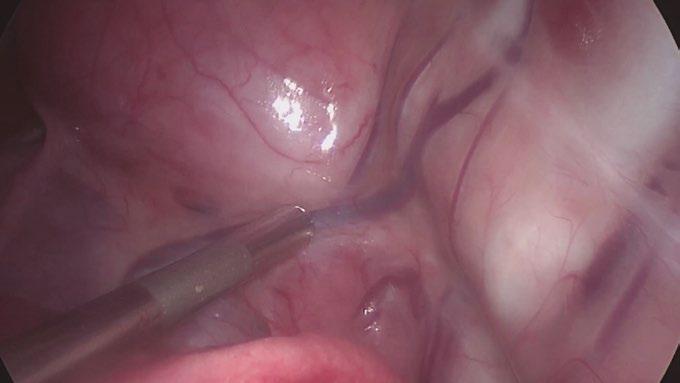

• Tratamiento toracoscópico de un cuarto arco aórtico derecho persistente y ligamento arterioso